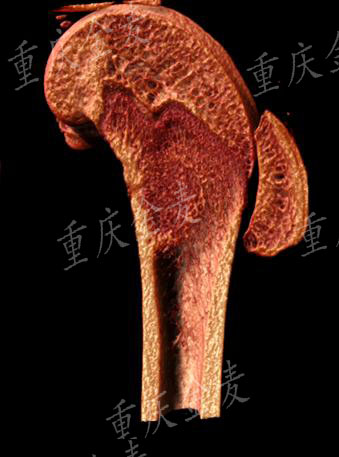

股骨髁外侧缺损μCT及三维成像

股骨髁外侧缺损材料修复μCT及三维成像